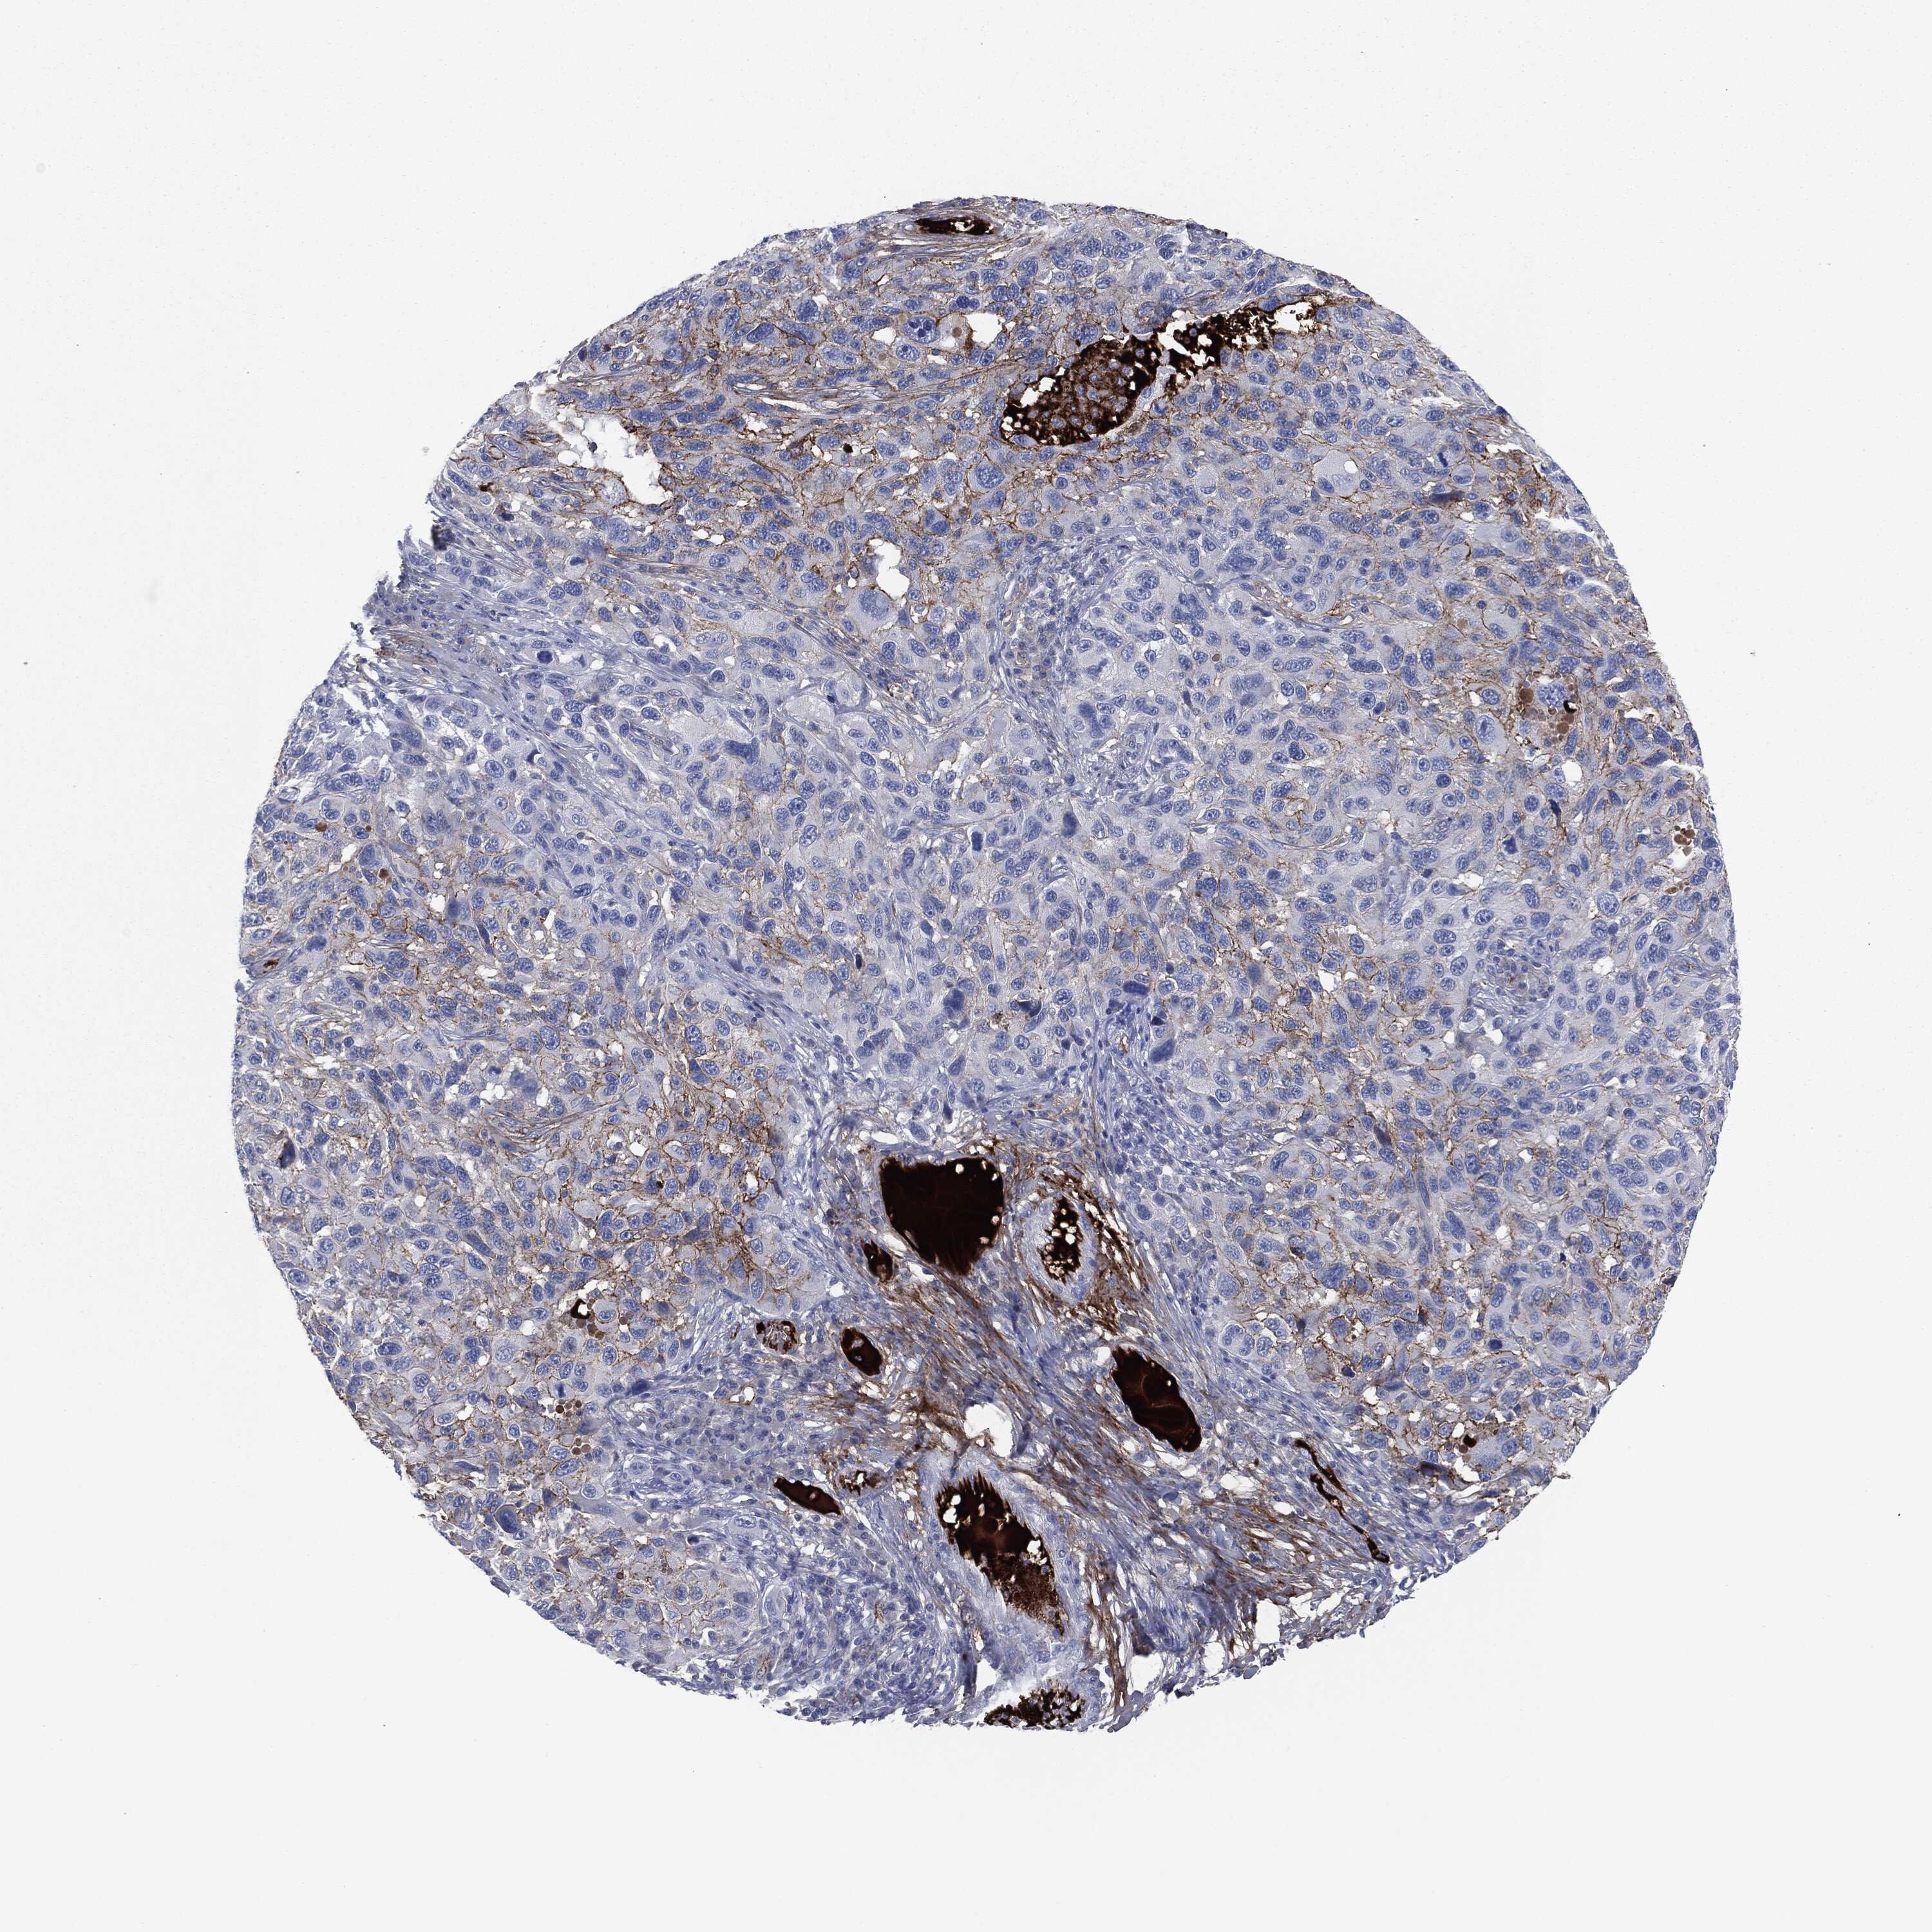

MELANOMA - Protein expressioni

A mouse-over function shows sample information and annotation data. Click on an image to view it in a full screen mode. Samples can be filtered based on level of antibody staining by selecting one or several of the following categories: high, medium, low and not detected. The assay and annotation is described here.

Note that samples used for immunohistochemistry by the Human Protein Atlas do not correspond to samples in the TCGA dataset.

Antibody stainingi

Antibody staining in the annotated cell types in the current human tissue is reported as not detected, low, medium, or high, based on conventional immunohistochemistry profiling in selected tissues. This score is based on the combination of the staining intensity and fraction of stained cells.

Each image is clickable and will lead to virtual microscopy that enables deeper exploration of all samples and also displays staining intensity scores, fraction scores and subcellular localization as well as patient and tissue information for each sample.

HPA049793

CAB016070

CAB080297

CAB080298

CAB080299

Malignant melanoma, NOS

Malignant melanoma, Metastatic site